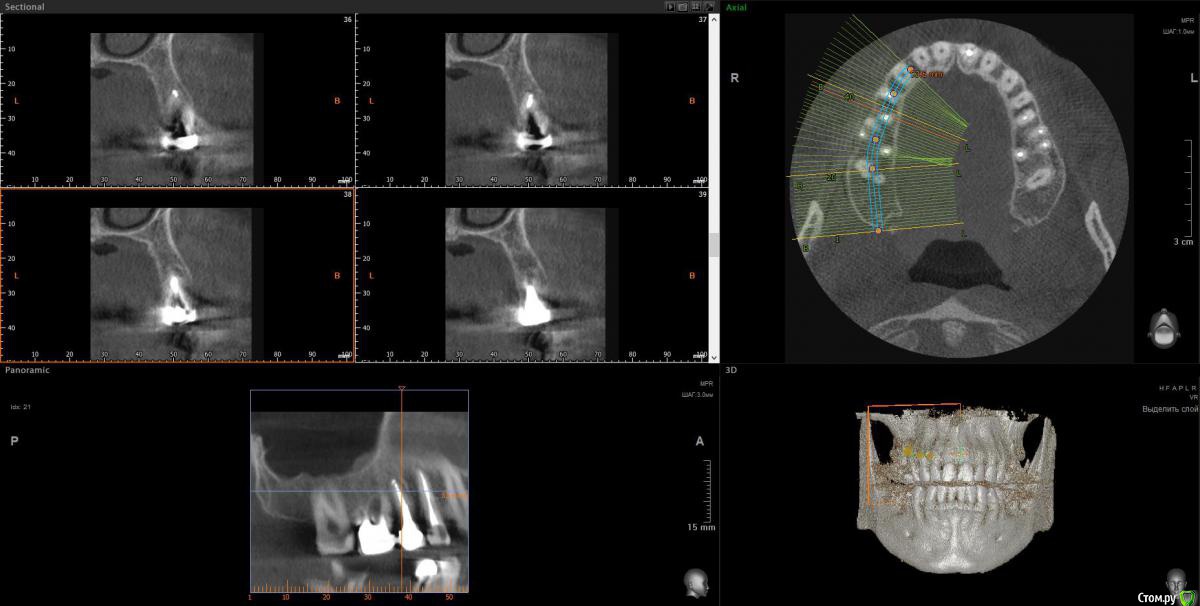

Taurus007 Опубликовано 9 февраля, 2018 Поделиться Опубликовано 9 февраля, 2018 После очных консультаций в разных клиниках (Москва) выяснилось много вариантов, что несколько смущает. Рекомендации и планы лечений такие:1.Удалить 15,16.25,26,37,47 . С учетом ранее удаленных 2х нижних шестерок, поставить 8 имплантов.При необходимости - подсадка костной ткани.2.Удалить 46,47,36,37,16,26, на их место импланты. 15,25 - поменять коронки. Дополнительно: а. Синус-лифтинг в различных комбинациях, либо без него. Мнения разные. б. Высказано мнение, что необходима коррекция прикуса, поскольку если его не трогать, а начать установку имплантов, то нагрузка на них будет чрезмерной, что повлечет рассасывание кости со всеми вытекающими. Сделал ТРГ, пока только снимок, анализ и расчет ТРГ на след. неделе будет готов. Из истории зубов: коронки стоят 9 лет, 35й - 1 год. Ссылки на ТРГ и компьютерную томографию . Сам я изначально склонялся к первому варианту. Без исправления прикуса.Подскажите, как все-таки лучше поступить? Важные вопросы: насколько необходимо исправление прикуса, и нужен ли синус-лифтинг, судя по КТ? Ссылка на комментарий

red_butler Опубликовано 9 февраля, 2018 Поделиться Опубликовано 9 февраля, 2018 насколько необходимо исправление прикуса для ответов нужно больше информации - http://forum.stom.ru/topic/4655-patcientam/ и нужен ли синус-лифтинг, судя по КТ? Выкладывайте срезы Кт, весь архив мало кто станет/сможет качать. 1 Ссылка на комментарий

wladdX Опубликовано 12 февраля, 2018 Поделиться Опубликовано 12 февраля, 2018 Скрины 1 Ссылка на комментарий

Bier Опубликовано 22 февраля, 2018 Поделиться Опубликовано 22 февраля, 2018 Справа синуслифтинг не потребуется 100%Слева - возможно в области 26 зуба. Для оценки прикуса одного ТРГ мало, надо еще фото моделей. Вам их наверное делали? Ссылка на комментарий

Taurus007 Опубликовано 24 февраля, 2018 Автор Поделиться Опубликовано 24 февраля, 2018 Справа синуслифтинг не потребуется 100% Слева - возможно в области 26 зуба. А в целом, можно ли сейчас не трогать область, где возможно потребуется синуслифтинг, поскольку в практическом смысле это наименее проблемная область, хоть коронки и стоят уже 9 лет ? надо еще фото моделей. Вам их наверное делали? Не делали. Это как-то в домашних условиях возможно? Ссылка на комментарий